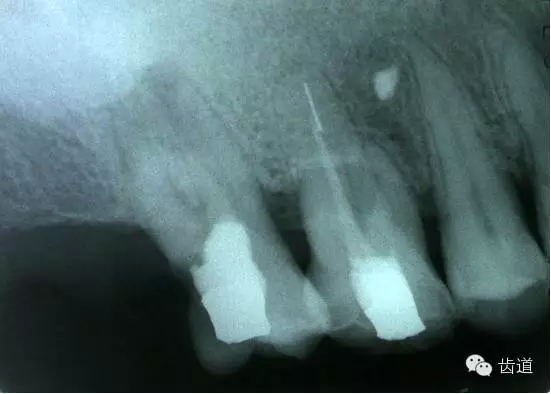

五、下唇麻木

(一)發(fā)生原因:主要由下齒槽神經(jīng)損傷所致

1.治療操作中藥物、器械或根充物超出根尖孔,進(jìn)入下頜管損傷下齒槽神經(jīng)

2.解剖因素:下頜牙齒根尖距下頜管太近,有些牙根與下頜管相連,以下頜第二恒磨牙多見(jiàn)

左下7根充后下唇麻木

左下5根管預(yù)備后下唇麻木

(二)處理:

1.根據(jù)病史認(rèn)真查找原因,如為炎癥刺激所致,應(yīng)積極治療根尖周炎,加口服營(yíng)養(yǎng)神經(jīng)藥物。

2.理化刺激所致,口服營(yíng)養(yǎng)神經(jīng)藥物。

(三)預(yù)防:

1.作根管治療前拍X線片,下頜牙齒應(yīng)特別注意與下頜管的關(guān)系。

2.準(zhǔn)確測(cè)量根管工作長(zhǎng)度,各種操作均在工作長(zhǎng)度范圍內(nèi)進(jìn)行。根管封藥不可過(guò)飽和,防止藥液溢出根尖孔。